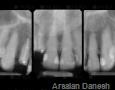

Pictures

Baseline